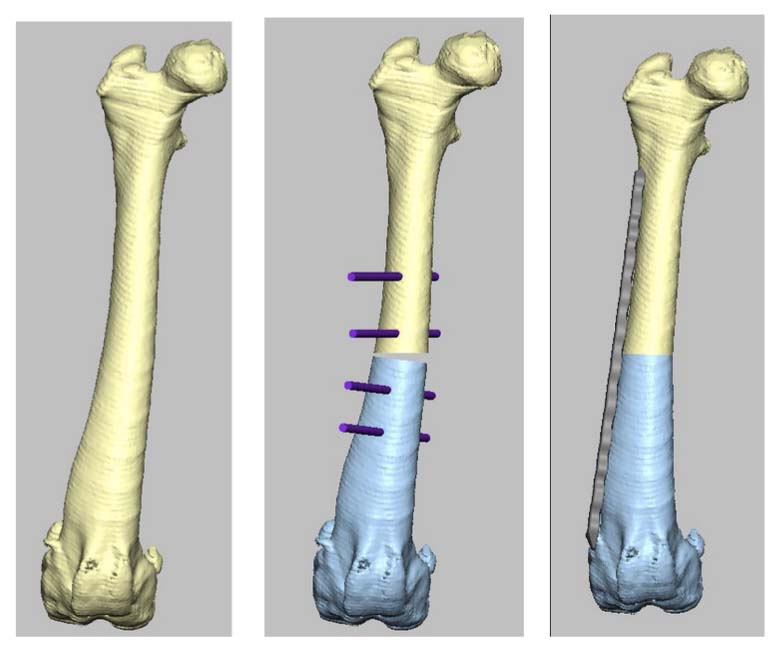

Correct the right femur angular limb deformities with a mid-diaphyseal oblique closing-wedge ostectomy centered at the CORA of the femoral deformity, which is located within the mid-diaphyseal (do not recommend a traditional distal femoral ostectomy (DFO) as this would result in a significant lateral femoral translation in this specific case). The trochlea is arthritic and hypoplastic, but not overtly deformed. In this case, a traditional block or wedge trochleoplasty is recommended rather than a patellar groove replacement (PGR). In addition, a corrective de-torsional tibial osteotomy has been recommended, as a tibial tuberosity transposition (TTT) is unlikely able to compensate for a torsion of this magnitude.

CT CAD-based surgical plan.

Right femoral mid-diaphysis bi-planar de-torsional medially based closing wedge ostectomy and internal fixation (lateral contoured locking straight plate and screws (Ti))